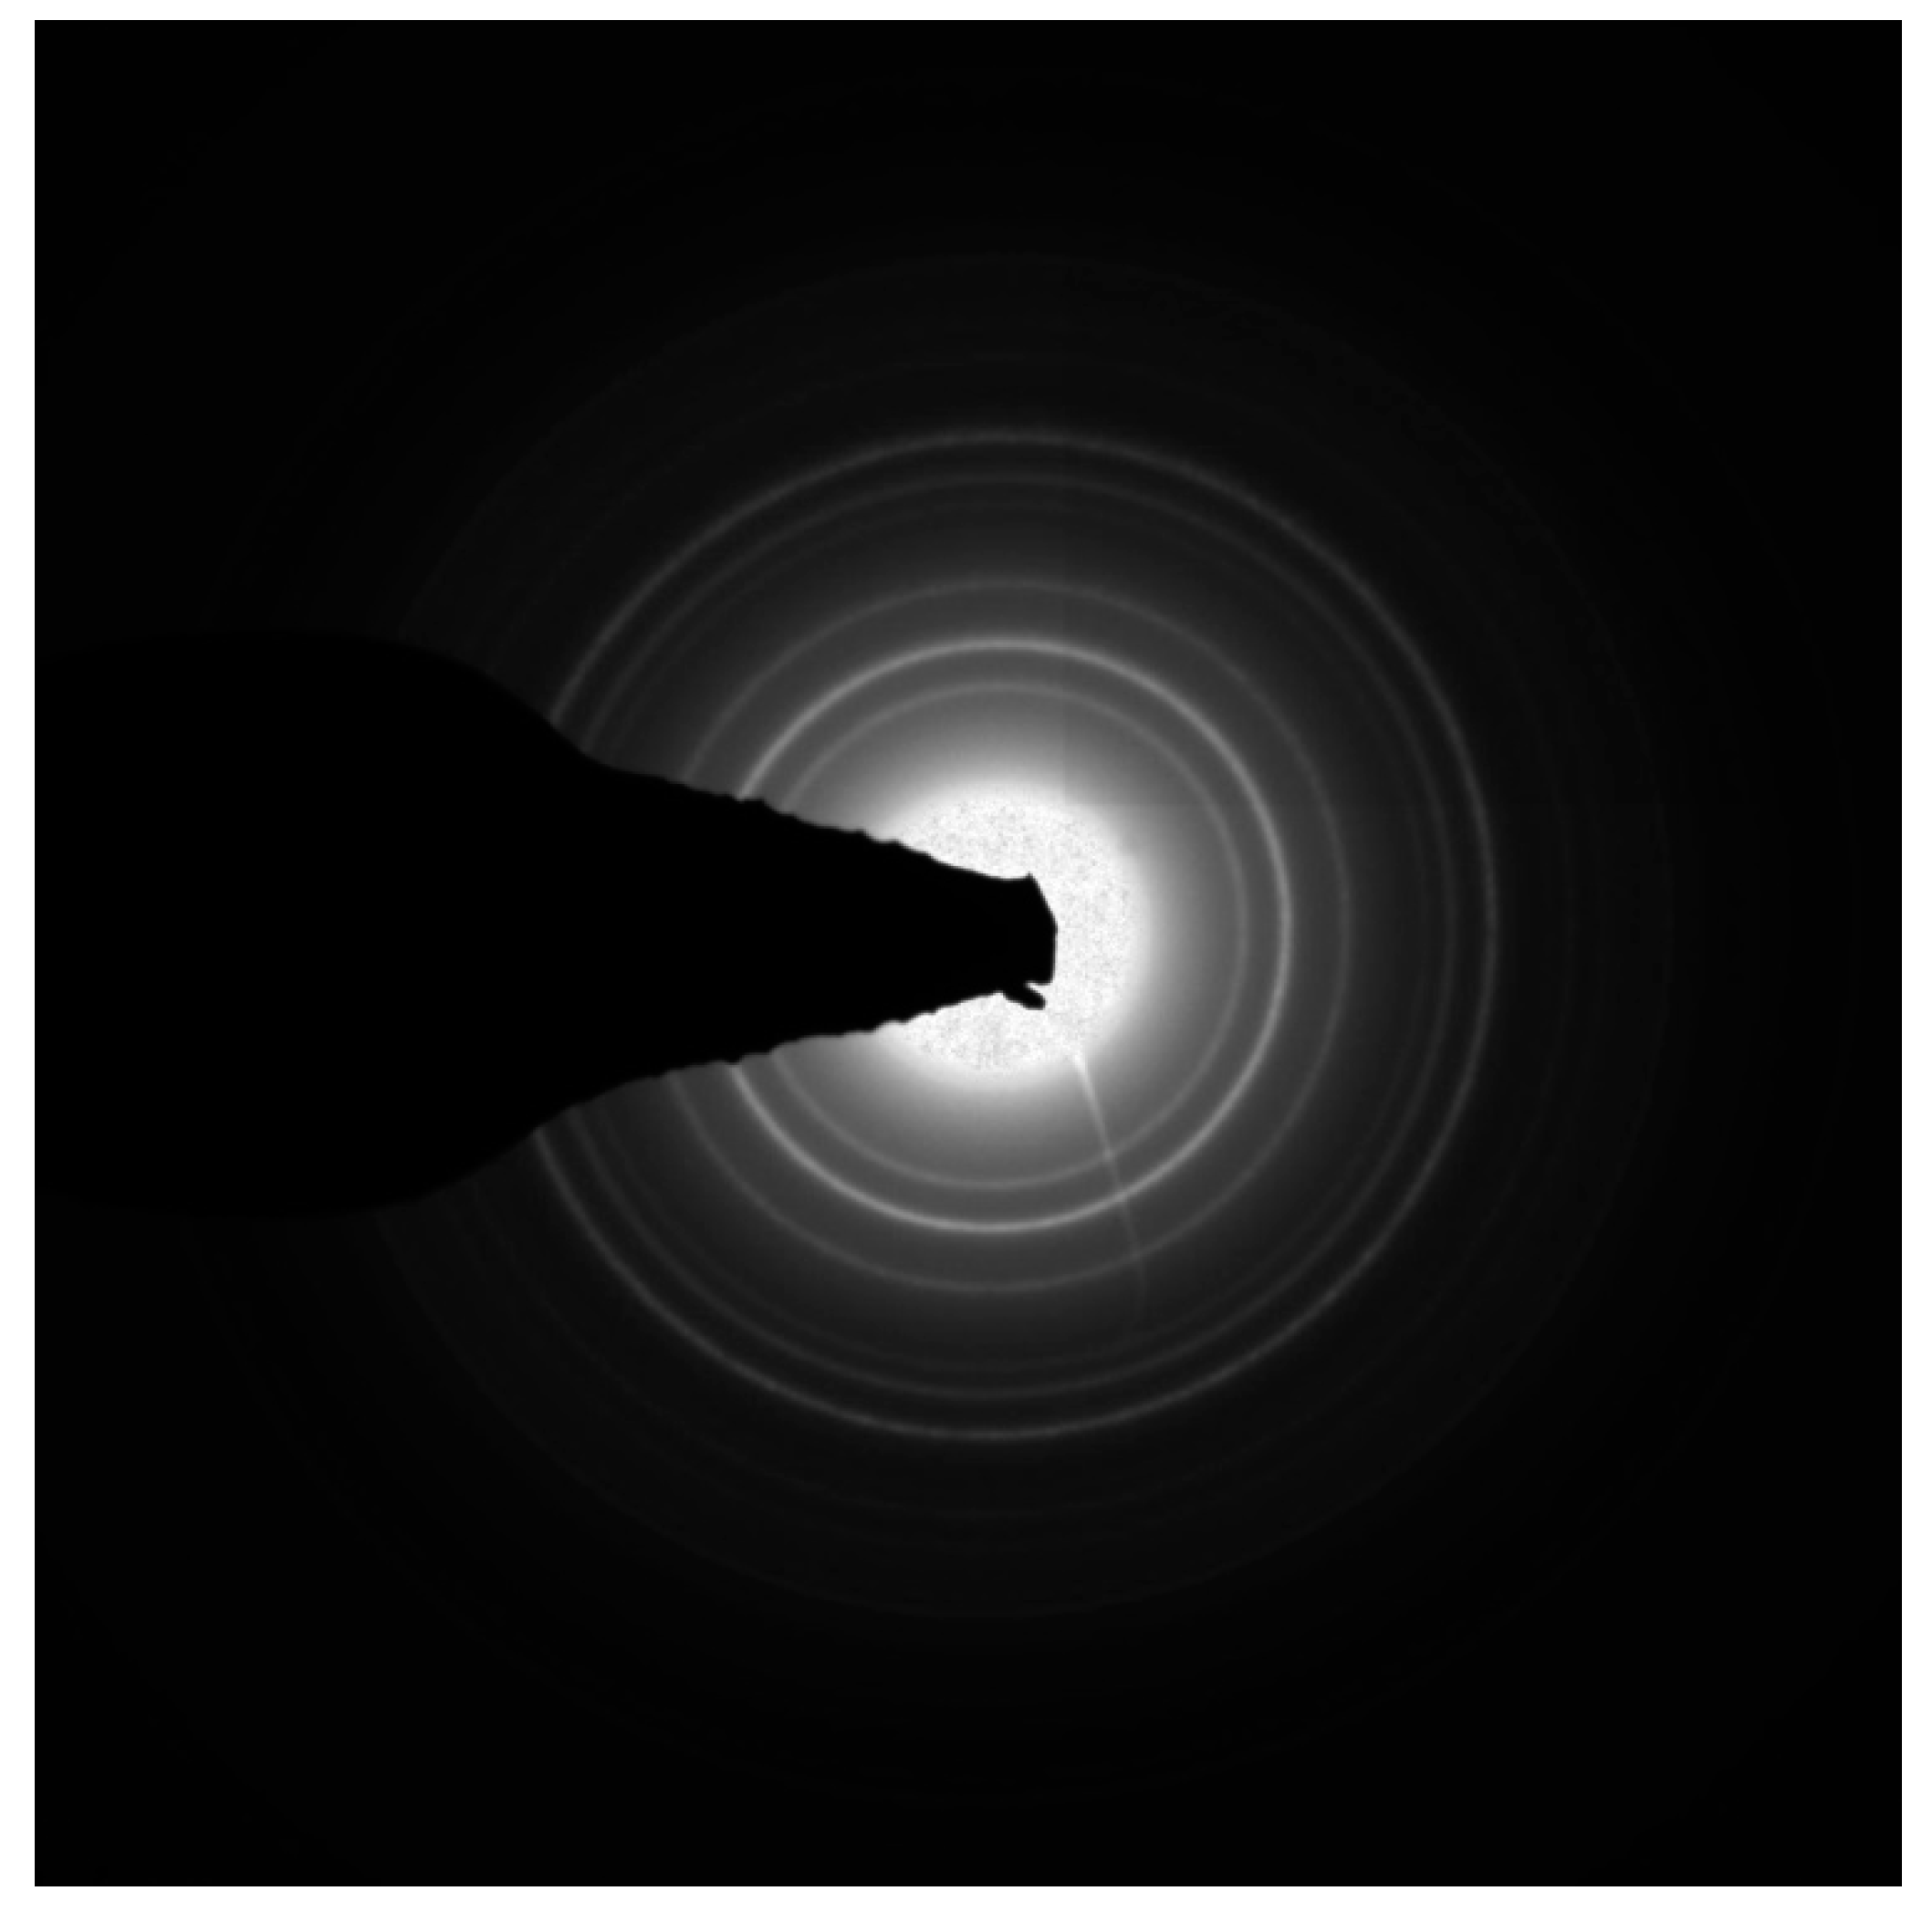

3.1. Synthesis of Pluronic F127- Folate coated and F127 coated SPION

3.2. Particles Size and Zeta Potential

3.2.1. Size of Particles